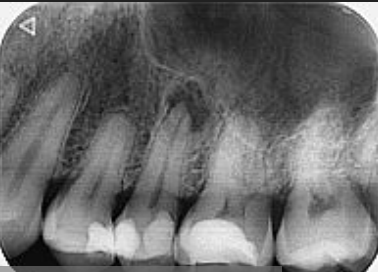

- Diagnosi Precisa: Una diagnosi accurata è il primo passo cruciale. Presso il nostro studio dentistico, utilizziamo moderne tecniche di imaging, come la radiografia digitale, per esaminare attentamente l’area coinvolta e identificare la presenza di granulomi apicali. La tc cone beam rappresenta un’indagine radiologica 3D ad alta definizione che consente di individuare granulomi anche laddove le tradizionali rx endorali dovessero fallire.